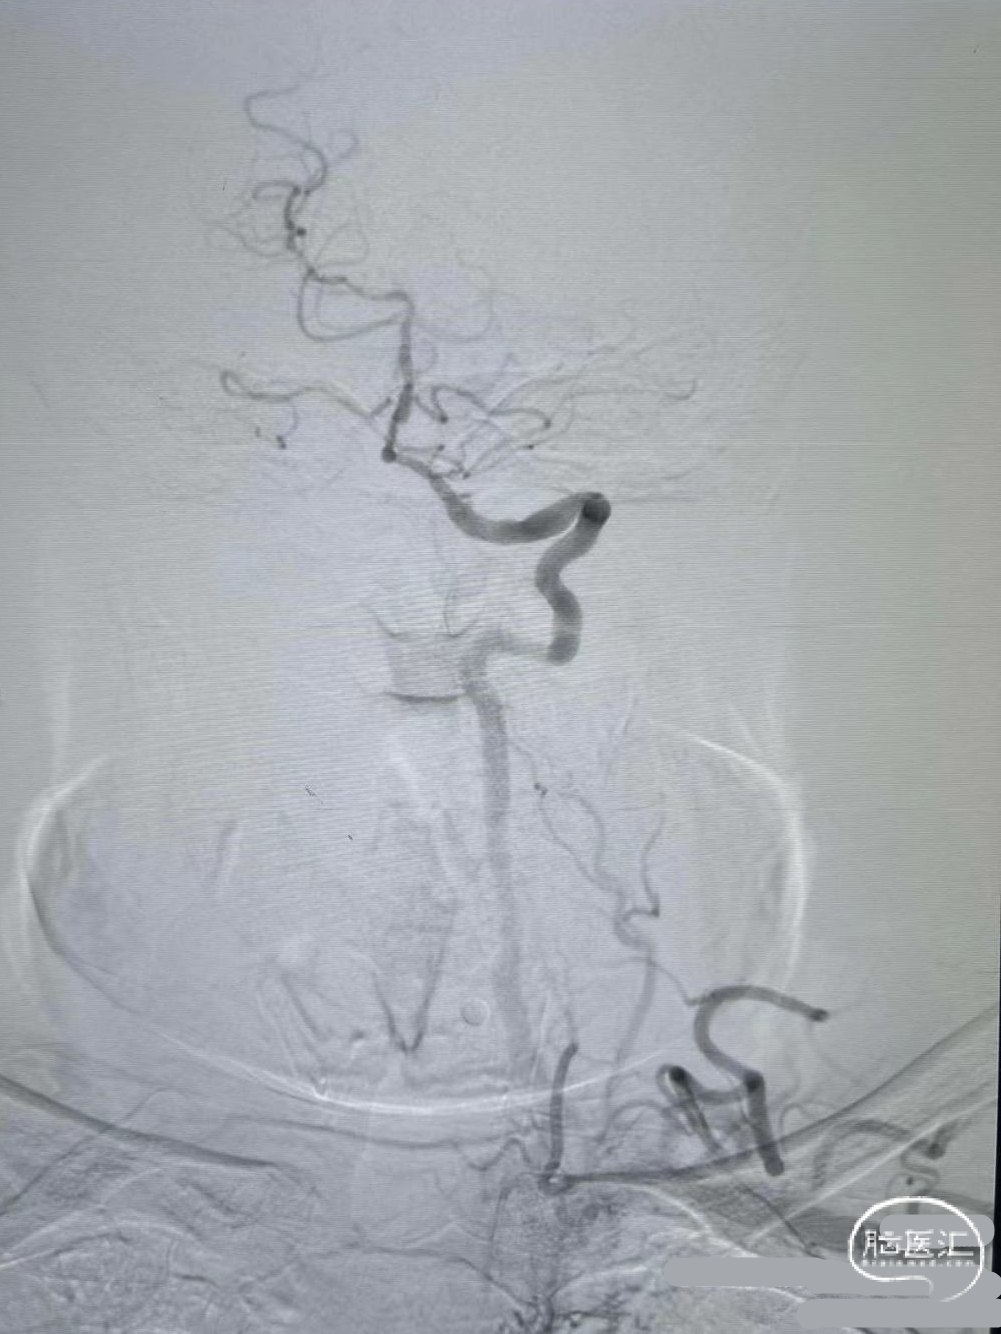

支架释放:

释放4mm*25mm Neurohawk取栓支架,可见支架显影良好,支撑性好,远端打开良好。中间导管跟上抽吸-SWIM技术。

支架回撤:

借助支架锚定,跟进中间导管至接触血栓,SWIM技术取栓一次,恢复血流。

保留微导丝、Guiding回撤到锁骨下,观察椎动脉开口:椎动脉开口无法维持。拟行椎动脉开口支架成形术,选用4mm*15mm Bridge椎动脉雷帕霉素靶向洗脱支架。

术后造影:

血管再通,前向血流3级。左侧为胚胎型大脑后。